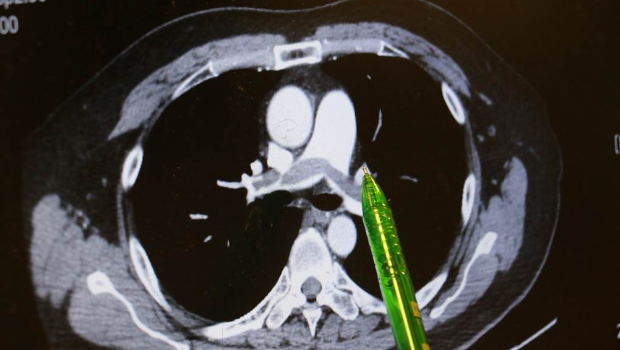

▲病人肺部两侧大片弥漫的血栓。台中慈济医院提供

谢姓男子不烟不酒,他自述上班久坐、在家也习惯久躺沙发,回想发病当天走楼梯时,短短一层楼竟像爬长陡坡,路过同事见他喘不过气、唇色发绿、冷汗直冒,催促紧急就医。台中慈济医院急诊医师检查发现患者血氧饱和度指数极低,电脑断层显示双侧肺动脉都有大块血栓,会诊心脏内科主任林茂仁确认是“双侧肺栓塞(Pulmonary embolism)”。

林茂仁说明,患者两侧肺叶弥漫大片血栓,属于临床典型而严重的“肺栓塞”,幸好他马上到急诊就医,还主述一周前曾出现“单侧小腿肿胀”的重要讯息,再透过相关检查,帮助医师快速查出病因。由于患者血液检查发现具有家族性先天凝血因子异常,显示体质天生比一般人有更多发生血栓的机会。